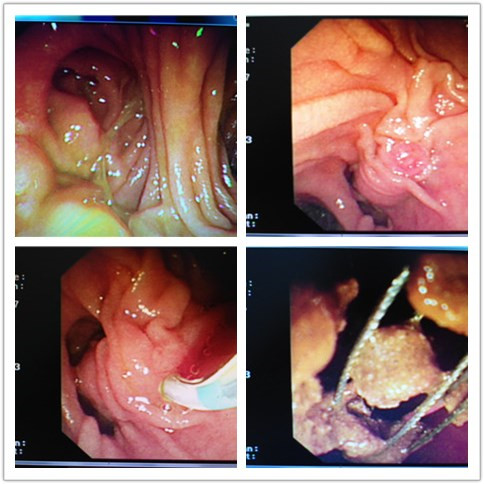

首先曹鹏医生对患者行术前胃镜检查,发现毕II式术后,患者肠管自胃吻合口分输入袢,输出袢,十二指肠乳头位于输入袢。找到十二指肠乳头后发现乳头与我们平时镜下看到的位置完全反转,由于内镜及所有附件均为正常结构下所设计,此例病人无法进行常规内镜下的十二指肠乳头扩管。怎么办?曹鹏医生没有放弃,他将乳头切开刀在体外进行塑形,经过反复尝试后终于插管成功,之后又使用与常规镜下操作完全相反的手法对患者进行胆管造影,可见胆管扩张,胆管内有两枚直径约1.8cm的巨大结石,随后行乳头括约肌切开+胆管末端柱状球囊扩张+机械网篮碎石取石+球囊清理+鼻胆管引流,顺利将患者胆管内的巨大结石取出,免除患者外科开腹手术之苦。

内镜下手术过程